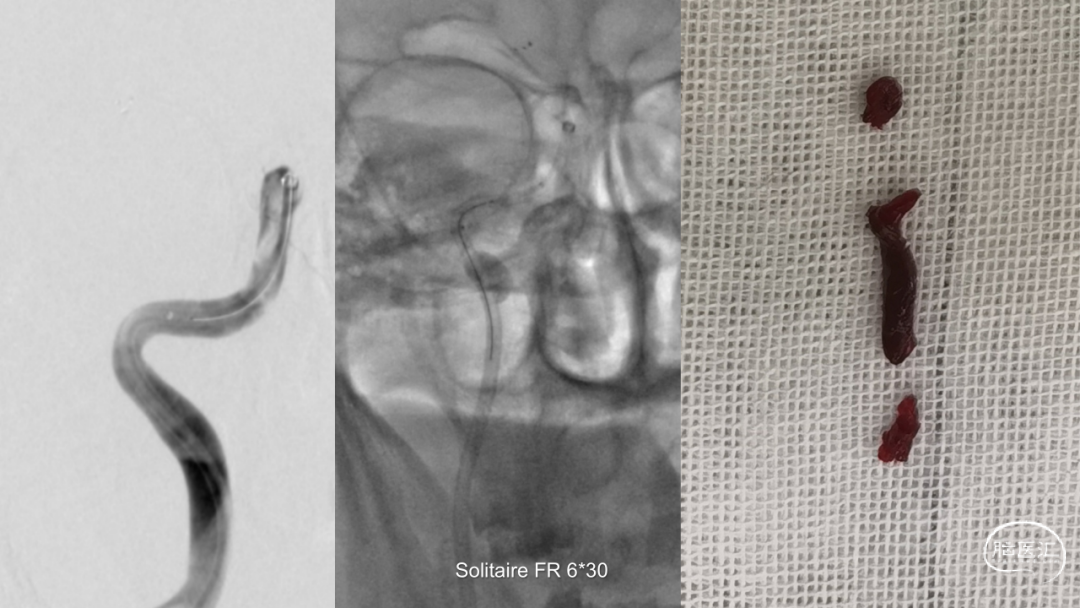

取之有道·第54期|李子付:Flowgate2取栓应用

看李子付解“取之有道”

滑动浏览更多内容